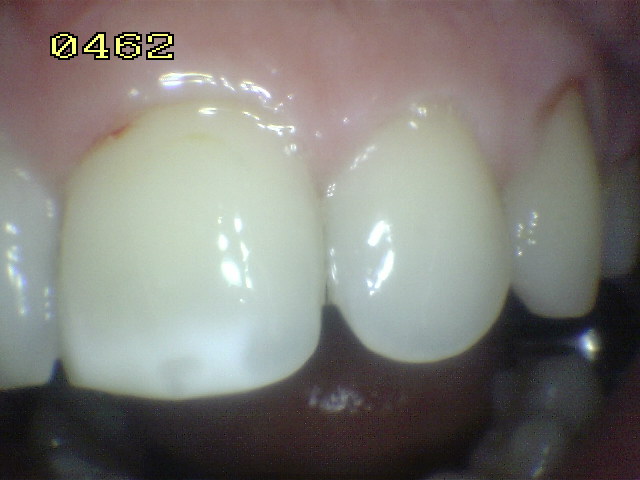

El examen visual debe emprenderse con los dientes completamente secos y con una buena iluminación.  El uso de amplificación de imagen también puede ayudar en el diagnóstico. El uso de una sonda se restringe al levantamiento de placa y detritos de comida.

El diente al lavarse y secarse con la jeringa triple deja expuesto esmalte blanquecino escarchado o opaco que delata un proceso de desmineralización, debido a que el agua se evapora de los microporos. Ver círculos rojos

Codificación  ICDAS y manejo individual de las lesiones

Código 1

Código 2

Código 3

Código 4

Una mancha oscura de dentina que se observa a través del esmalte intacto,  adyacente a la fosa y reborde marginal,  indica la presencia de desmineralización. (Imagen 0229)